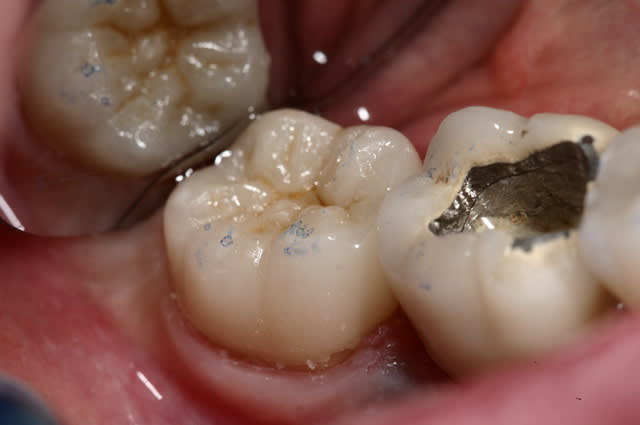

photo retrouvées :)

plus de place pour la ceramique, et plus de rétention dans l'endo que dans l'exo ;)

Pour répondre a ta réponse je fait endo couronne quand le volume de la chambre est superieur au volume du futur moignon ... j'ai fait des photos très parlantes que je retrouve plus :(